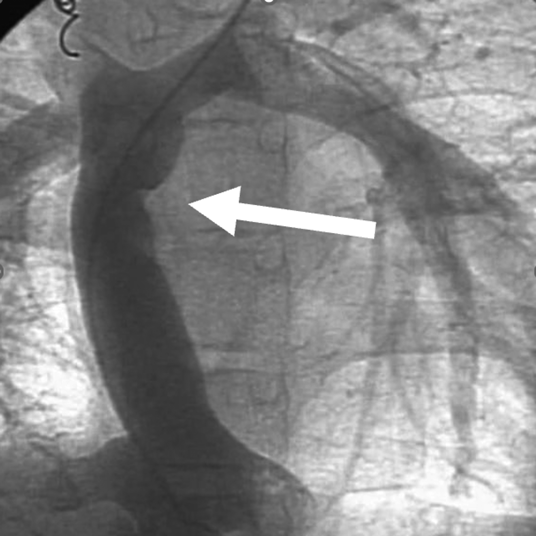

1か月健診で心雑音を指摘され,三尖弁閉鎖不全症(IIc型)と診断された.日齢41に肺動脈絞扼術を施行し,2歳4か月時に両方向性グレン手術,Damus–Kaye–Stansel(DKS)吻合,心房中隔欠損孔拡大を行った.3歳10か月時に心外導管型フォンタン手術(ePTFE: expanded polytetrafluoroethylene 20 mm)を施行した.9歳時の心臓カテーテル検査では,明らかな圧較差は認めないが,導管の一部にわずかに造影欠損を認めていた(Fig. 1).抗血栓薬は抗血小板薬のみを内服していた.19歳時に完全房室ブロックが出現し,ペースメーカー植え込みが必要となった.経胸壁心エコー検査にて中等度の新大動脈弁閉鎖不全を認め,心臓カテーテル検査・CT検査にて心外導管中央に狭窄を認め,同時手術目的に当科紹介となった.

Pediatric Cardiology and Cardiac Surgery 36(1): 84-89 (2020)

Fig. 1 Angiography in patient 1 at 9 years of age showing a contrast defect in the extracardiac conduit in patient 1